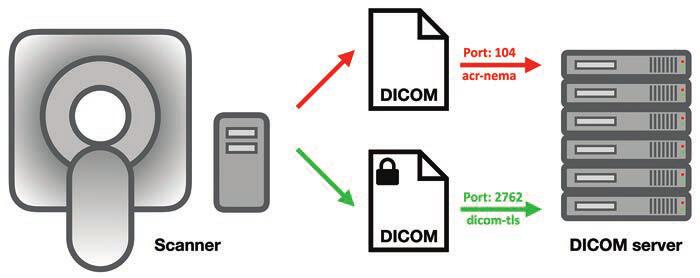

The HOD passed a pivotal resolution calling on AMA advocacy for federal health IT interoperability standards to include the DICOM format, a critical “missing link” that delegates have long championed. Despite over two decades of EHR development and federal mandates, DICOM has been excluded from formal interoperability frameworks. As a result, radiological images frequently cannot travel seamlessly through EHR systems, frustrating patients and providers alike. For one example, patients arriving for mammograms at new facilities are often dumbfounded that previous studies cannot be accessed digitally from elsewhere. The absence of interoperable imaging standards contributes to delayed care, redundant exams, unnecessary radiation exposure, and burdens for patients. And the security risks are legion (Fig. 1).

Fig. 1—Schematic shows DICOM server, computers that can exchange and store DICOM objects. Server offers DICOM service, which is software that can send and receive DICOM messages, running via specific computer ports (i.e., communications channels). Secured DICOM service is known as dicom-tls (port 2762), which uses transport layer security for negotiations, authentication, and encryption. A service that cannot be queried by hackers because it uses strong authentication mechanisms, this service sends and receives encrypted DICOM messages that cannot be read by hackers either. However, this is only true for manufacturers that have chosen to implement its strong authentication and encryption features. Arrows show direction of data transmission.

Spearheaded by neurology and orthopedic associations, this resolution urges inclusion of DICOM in the U.S. Core Data for Interoperability (USCDI) and seeks regulatory action requiring EHR and imaging archive vendors to support secure, efficient exchange of DICOM data. Testimony also highlighted policy fissures stemming from the Health Information Technology for Economic and Clinical Health (HITECH) Act of 2009, which exempted radiologists—alas, not viewed as patient-facing—from certain data-sharing requirements, thereby keeping imaging outside USCDI [2]. A significant win for medical imagers across the country, delegates did have to amend the resolution to get it passed, but this is meaningful progress toward closing the interoperability gap that hampers timely, coordinated, and secure care.